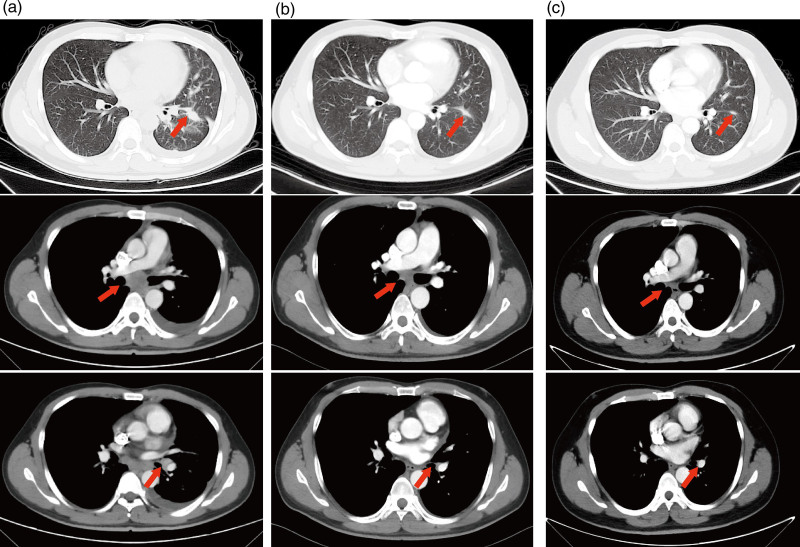

The novel and highly selective anaplastic lymphoma kinase ( ALK ) inhibitor iruplinalkib showed potent activity and manageable safety profiles in patients with ALK -rearranged non-small cell lung cancer (NSCLC). However, the evidence of iruplinalkib for uncommon ALK double fusion and secondary G1202R resistance mutation is limited. Here, we report a case of a 36-year-old male with metastatic NSCLC harboring uncommon TTC7A - ALK and EML4 - ALK double fusion. Alectinib as first-line therapy showed partial response, with a progression-free survival (PFS) of 20 months. When his disease progressed, the ALK secondary G1202R resistance mutation was identified. His metastatic paraesophageal lymph node decreased during iruplinalkib treatment, achieving an ongoing PFS benefit for 10 months. Treatment-related adverse events of iruplinalkib were grade 1 hypercholesterolemia and hypertriglyceridemia. The modeling simulation revealed that the G1202R mutation exerted little effect on the binding of iruplinalkib. Iruplinalkib showed potency to G1202R because of its unique chemical structure and removal of steric clashes, which might be a promising option for ALK -rearranged NSCLC patients with G1202R resistance mutation.